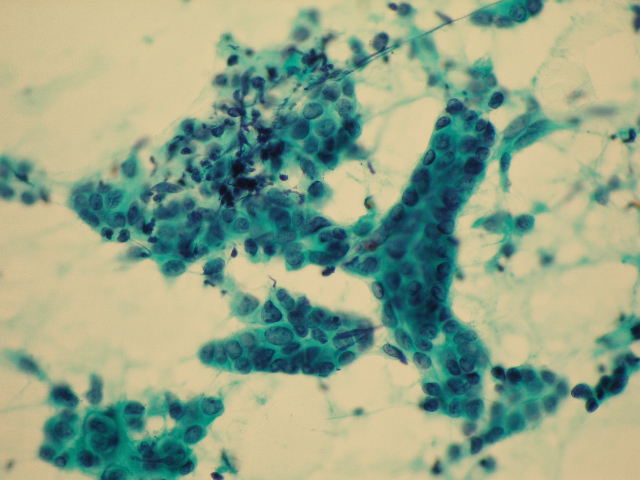

- (3)細胞診判定および診断

- 病変部の擦過や注射針による穿刺吸引物、喀痰、尿、体腔液(胸水、腹水など)などの検体から標本を作製し顕微鏡で観察して、がん細胞などの有無を確認する検査です。組織診断と異なり、非侵襲性で迅速かつ簡便で、ある程度の反復検査が可能です。細胞診標本は細胞検査士が鏡検し報告しますが、異型細胞がみられた症例に関しては細胞診専門医が最終的な診断を確定します。特別な症例を除き報告までに2日程度を要します。

細胞診材料

異型細胞(肺癌・角化型扁平上皮癌)

異型細胞(乳癌・腺癌)